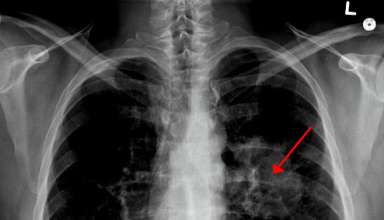

Pažnja: Ovo su simptomi za rano otkrivanje raka Pluća.

Mnogi ljudi rak pluća odmah povezuju sa smrću, što je na neki način prihvatljivo, s obzirom da godišnje veliki broj ljudi umire od raka pluća. Ipak, kada se rak pluća otkrije dovoljno rano, on se …